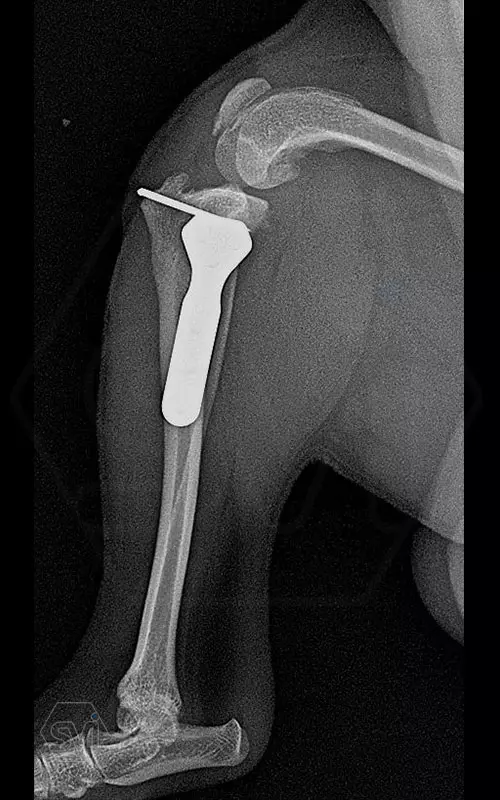

Introducing the TPLO-M „terraced” plate family from Smartvetimplants.com

In small dogs, medial patella luxation (MPL) and the rupture of anterior cruciate ligament (RACL) often occur simultaneously. During the surgical procedure, the joint must be stabilized and the patella fixed in the middle axis at the same time.

The solution of Smatvetimplants is the TPLO-M plate family with terrace:

Small TPLO-M plate:

part of a polyaxial locking system, symmetrical, available with 2.5 and 4.0mm terraces, torx-head, 2.4mm locking screws (2.0 and 2.4mm AO screws can also be inserted), material steel. Optimized for R12 and R15 blades.

Between October 2020 and December 2021, we performed 19 TPLO-M surgeries at the Animal Hospital in Nyíregyháza,: 16 times used the mini (2.0 R12) and 3 times the small (2,4 R15) TPLO-M plate.

The experience is very encouraging, we find the system and plates suitable for the simultaneous treatment of MPL and RACL. ( in case of 4/4 pat. lux. also). We will back soon with details.